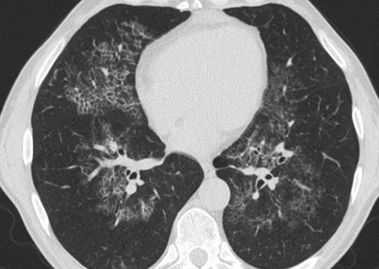

КТ имеет высокую чувствительность в выявлении изменений в легких, характерных для COVID-19. Применение КТ целесообразно для первичной оценки состояния ОГК у пациентов с тяжелыми прогрессирующими формами заболевания, а также для дифференциальной диагностики выявленных изменений и оценки динамики процесса. КТ позволяет выявить характерные изменения в легких у пациентов с COVID-19 еще до появления положительных лабораторных тестов на инфекцию с помощью МАНК. В то же время, КТ выявляет изменения легких у значительного числа пациентов с бессимптомной и легкой формами заболевания, которым не требуется госпитализация. Результаты КТ в этих случаях не влияют на тактику лечения и прогноз заболевания при наличии лабораторного подтверждения COVID-19. Поэтому массовое применение КТ для скрининга асимптомных и легких форм болезни не рекомендуется.

3. Применение лучевых методов у пациентов с симптомами ОРВИ легкой степени тяжести и стабильном состоянии пациента, возможно только по конкретным клиническим показаниям, в том числе при наличии факторов риска, при условии достаточных технических и организационных возможностей. Методом выбора в этом случае является КТ легких по стандартному протоколу без внутривенного контрастирования или РГ при ограниченной доступности КТ. Использование УЗИ в этих случаях нецелесообразно. Применение КТ исследования в сроки ранее 3 - 5 дней с момента появления симптомов заболевания является нецелесообразным.

4. Все выявляемые при лучевых исследованиях признаки, включая КТ-симптомы, не являются специфичными для какого-либо вида инфекции и не позволяют установить этиологический диагноз. Вне клинической (эпидемической) ситуации они не позволяют отнести выявленные изменения к пневмонии COVID-19 и дифференцировать их с другими пневмониями и невоспалительными заболеваниями. Данные лучевого исследования не заменяют результаты обследования на РНК SARS-CoV-2. Отсутствие изменений при КТ не исключают наличие COVID-19 и возможность развития пневмонии после проведения исследования.